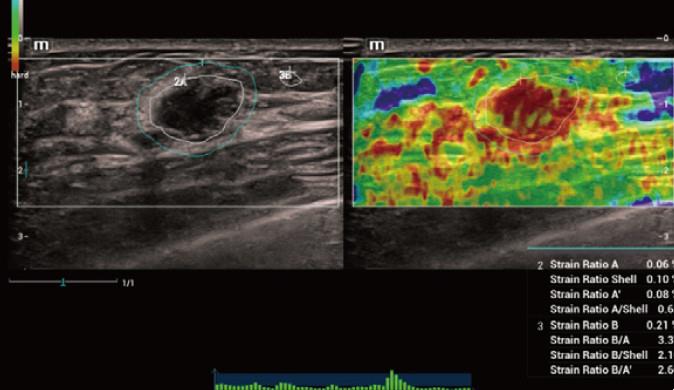

2、實(shí)時彈性成像Natural Touch Elastography

采用最新的專利彈性成像技術(shù),提升彈性圖像的敏感性,降低了對操作者手法的依賴。獨(dú)有的Shell功能,有效評估腫塊對周邊組織浸潤程度。